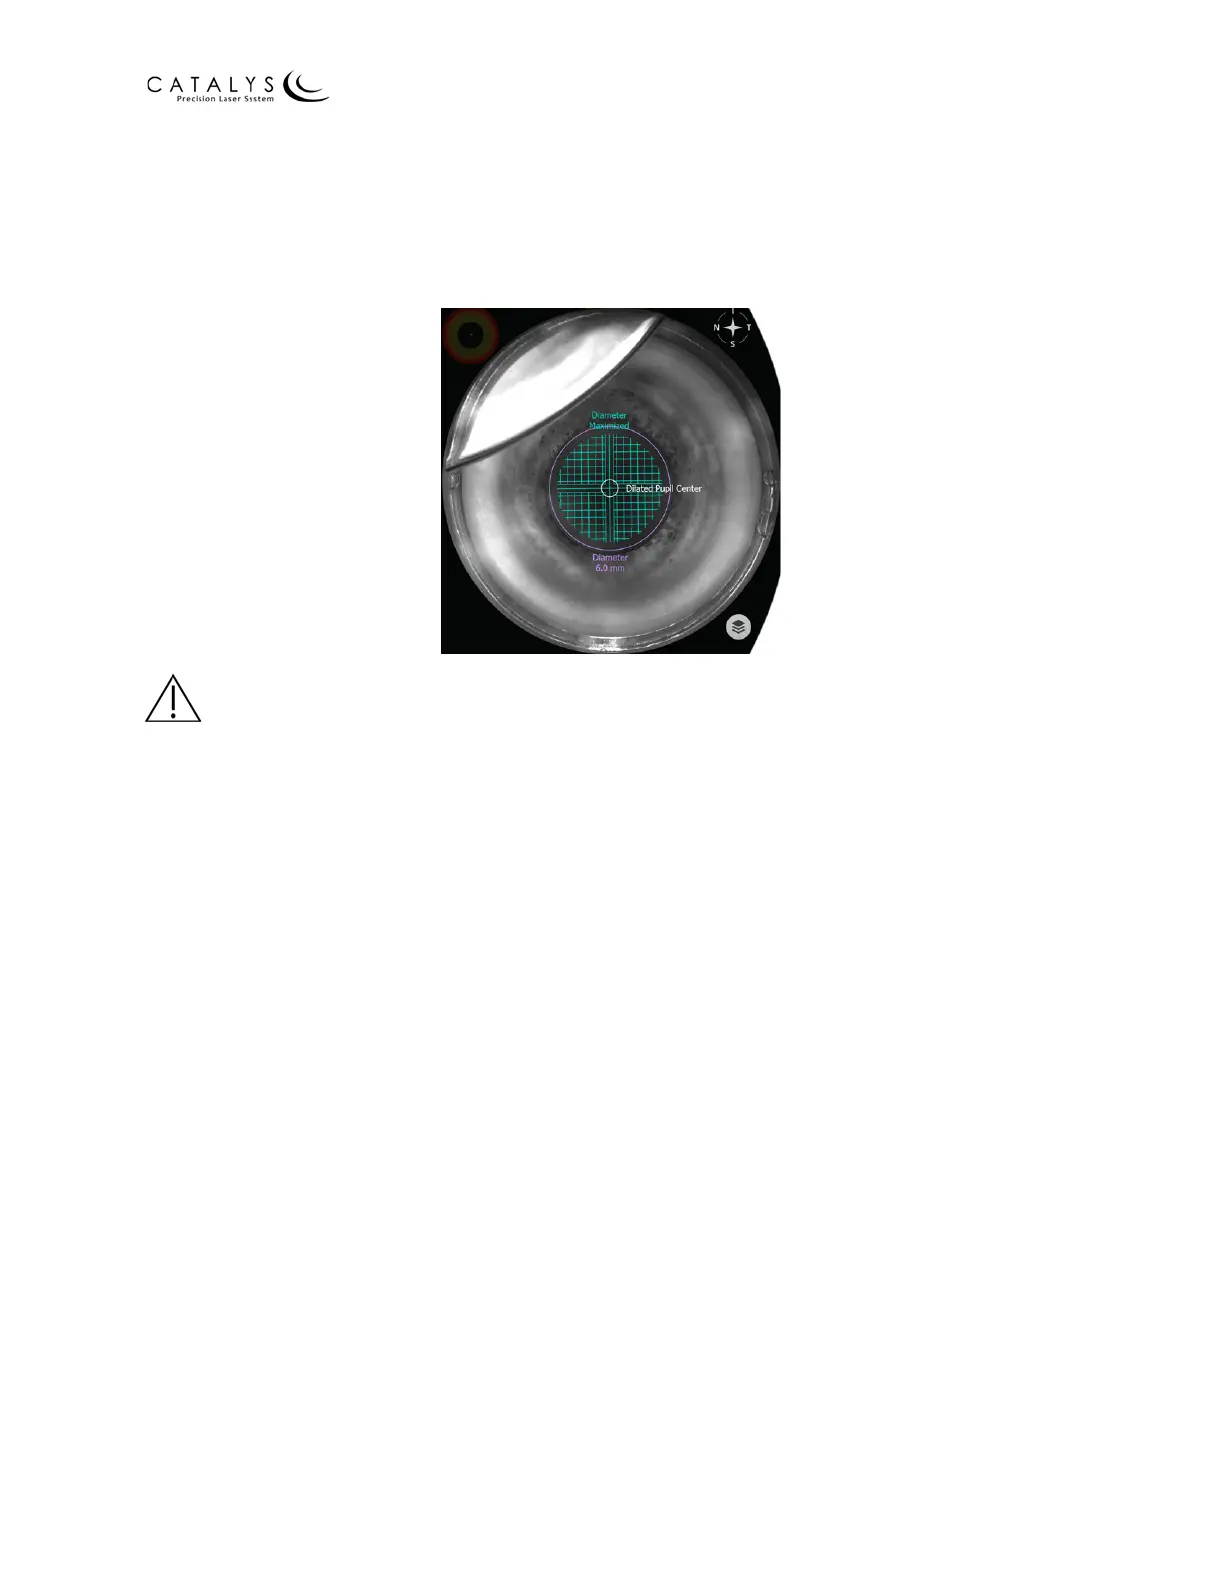

Figure 3.112 Meniscus on Video Image

WARNING

Continuously verify that the eye has not moved with respect to its initial presentation at the time

of fluid confirmation. If the eye moves during INTEGRAL GUIDANCE System imaging, press the

RESCAN EYE button. If the eye moves during laser treatment, terminate the laser treatment by

immediately releasing the laser footswitch.